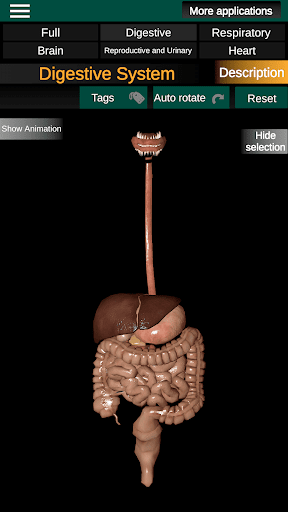

* Spijsverteringsstelsel, inclusief de maag, dunne darm, dikke darm, en een animatie van dit systeem.

* Gemakkelijk te openen en te navigeren (zoom, 3D-rotatie).

* Beschrijvingen van elk orgel.